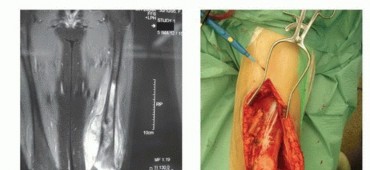

- التصوير بالرنين المغناطيسي (MRI): يوفر الرنين المغناطيسي صورًا تفصيلية للعظم والأنسجة الرخوة المحيطة، مما يساعد في تحديد حجم الورم وامتداده وعلاقته بالأوعية الدموية والأعصاب.

جراحة زرع الطرف الصناعي القابل للتمدد

تُعد جراحة زرع الطرف الصناعي القابل للتمدد عملية معقدة تتطلب فريقًا جراحيًا متخصصًا وخبرة واسعة. يقود الأستاذ الدكتور محمد هطيف هذه الجراحات بدقة ومهارة عالية في صنعاء، ويضمن الالتزام بأعلى المعايير الجراحية.

- التصوير المتقدم: يتم إجراء أشعة رنين مغناطيسي (MRI) وأشعة مقطعية (CT) مفصلة للورم والعظم المحيط لتخطيط الجراحة بدقة فائقة، وتحديد هامش الاستئصال الآمن.

- التخطيط الجراحي: يقوم الأستاذ الدكتور هطيف والفريق الجراحي بتخطيط دقيق لكل خطوة من خطوات الجراحة، بما في ذلك تحديد نوع الطرف الصناعي القابل للتمدد وحجمه، ومسار الشق الجراحي، وكيفية إعادة بناء الأنسجة الرخوة.